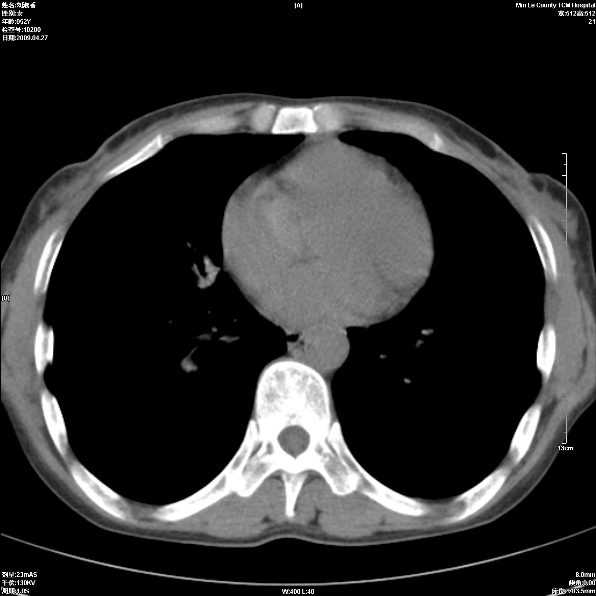

标题: CT19625:女52间断性喀血 [打印本页]

标题: CT19625:女52间断性喀血

考虑右肺中叶感染性病变并右肺中、下叶肺泡积血;建议抗炎、止血治疗后复查。

右肺中叶炎症;右肺中、下叶肺泡积血

考虑 右肺中叶感染性病变伴右肺中下叶肺泡积血。

考虑右肺中叶感染性病变并右肺中、下叶肺泡积血。建议治疗后复查。